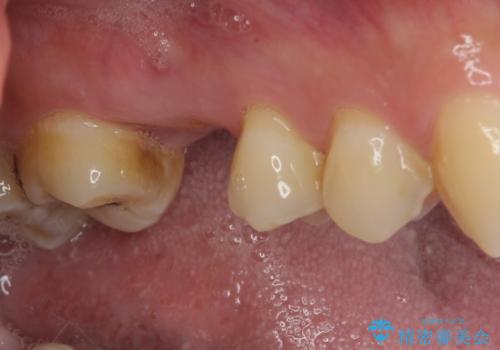

強い痛みのあった歯は、既に神経組織が失活しており根管治療が必要でした。

反対側の歯は、歯根だけが歯肉に埋もれて残っている状態のため、抜歯が必要な状態でした。